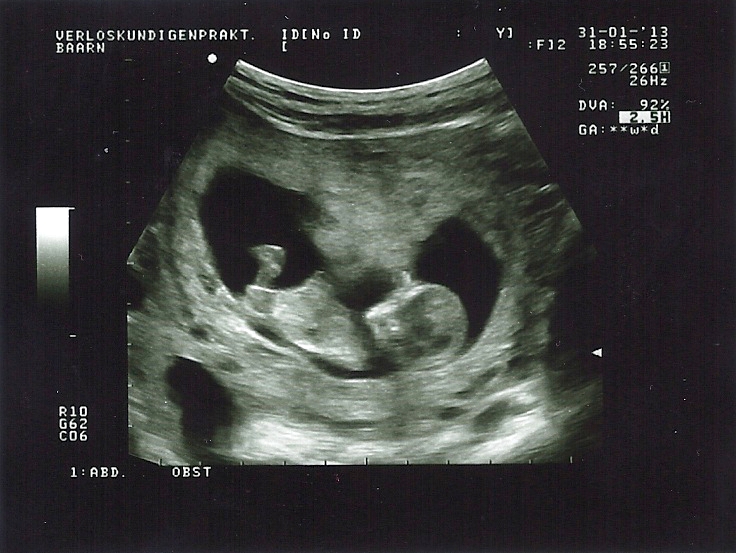

I am not sure if I see a nub in one of these pictures. Maybe the first and last? Any ideas? My mw is leaning towards girl, but on screen it looked a lot clearer than on these photo's... This was this evening, exactly 12w. Thank you for taking a look!

Thread updated with confirmed 15w u/s girl pictures :-)